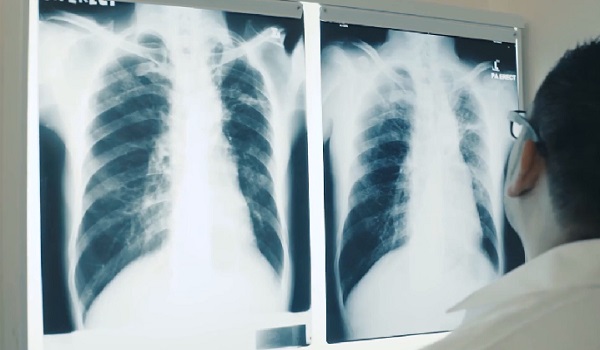

Tiada bukti radiasi PPUM sebabkan kluster kanser

- BKRP jalankan siasatan menyeluruh menilai keselamatan radiasi dan pematuhan mengikut Akta 304.

- Keselamatan pesakit, pekerja dan orang awam jadi keutamaan dengan pemantauan dan audit pematuhan berkala.

- Orang ramai dinasihatkan tidak buat spekulasi; KKM komited berkongsi maklumat tepat berasaskan bukti teknikal.